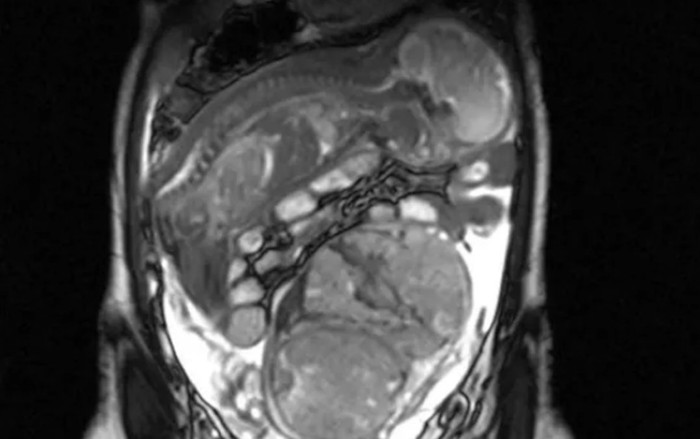

Hình ảnh siêu âm cho thấy thai nhi nằm trên đỉnh bụng mẹ, úp mặt xuống dưới.

Sau khi thăm khám và chụp siêu âm, bác sĩ phát hiện thai nhi vẫn phát triển bằng cách bám vào ruột của mẹ. Người phụ nữ sụt 3kg trong vòng hai tuần và bị thiếu máu, mặc dù các dấu hiệu sinh tồn đã ổn định.